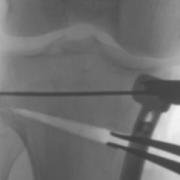

Osteotomy entails cutting into the bone, and either opening up a wedge-shaped gap and fixing it in the new position, or removing a wedge of bone and again fixing the position with a plate and screws. The common osteotomy for a varus problem is called a high tibial osteotomy.

Here you can see a guide wire, the cut in the bone (paler than the bone) which is being wedged the correct amount using a laminar spreader which holds it in place until the plate and screws are in place. Bone graft can be used to fill the gap, or it can be left to grow new bone by itself (which makes the rehabilitation a bit longer).